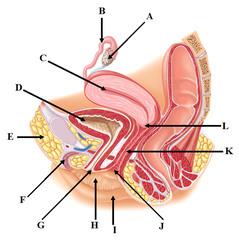

Bulbourethral gland (male)

Bulbourethral gland (female)

Ejaculatory Duct

Epididymis

External urethral orifice (male)

External urethral orifice (female)

Prostate gland

Prostatic/spongy urethra (males)

Scrotum

Seminal vesicle

Seminiferous tubule

Testis (s.) Testes (pl.)

Ureter

Urethra

Urinary Bladder (male)

Urinary Bladder (female)

Vagina

Vas deferens (=ductus deferens)